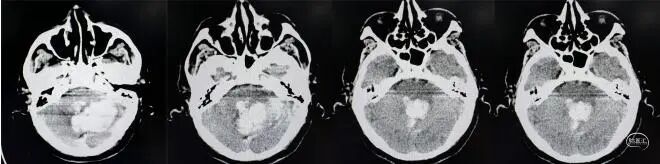

患者79岁高龄,入院前突发头痛、头晕、恶心呕吐,呕吐物为咖啡色胃内容物,伴步态不稳,紧急就诊于外院,头部CT提示“左侧小脑出血、梗阻性脑积水”。小脑出血10毫升以上即达到手术干预的关键阈值,而该患者小脑出血量高达48毫升,加之梗阻性脑积水对脑组织的压迫,患者随时面临脑疝风险,生命垂危。

患者病情危重,且既往因肾盂肾癌已行肾摘除手术,外院已不建议手术治疗,已在外院保守治疗2天,但家属治疗意愿强烈且陷入困境,他们经多方打听,通过吉大一院神经创伤外科中心付双林主任介绍,得知李晓东主任在重症颅脑疾病救治领域的深厚造诣,果断寻求帮助。李晓东主任接到求助后,立即组织团队对患者病情进行全面研判:患者不仅小脑出血量大、合并梗阻性脑积水,而且因既往肾盂肾癌单侧肾切除史,术前肾功能已出现异常(肌酐305μmol/L),手术风险与术后并发症概率大幅升高。

患者术前头部CT▲